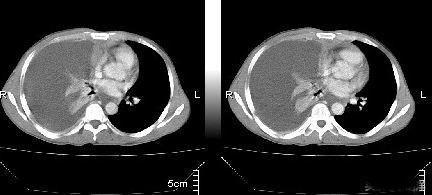

结核性胸膜炎是结核菌感染胸膜所致的疾病,胸膜大家可能不太了解,它是肺外面被覆的两层膜性组织,一层与肺融为一体,称为脏层胸膜,靠近肺外周的肺小叶生根于脏层胸膜,更外面一层胸膜成为壁层胸膜,与胸壁内侧融为一体,这两层胸膜在肺的最底层肋膈角部位连接,形成一个密闭的腔,称为胸腔,正常情况下胸腔内有少量的液体起到润滑作用,其中为纯净无微生物的空间。

结核性胸膜炎会有很明显的胸痛症状,这个症状可以为隐痛也可以为剧烈的疼痛,并且和呼吸相关,深吸气是疼痛的程度会加大,这是由于胸膜上除了密布血管和淋巴管之外,痛觉神经也非常丰富,有炎症时更加敏感,两层贴在一起的胸膜随着呼吸会发生相对的运动产生摩擦,这时候就会引起剧烈的疼痛感。但这种疼痛感会随着胸腔积液的产生和增多而逐渐减弱和消退,这是由于胸腔积液产生后就会隔开两层胸膜不会产生摩擦而致。除了胸痛之外,结核性胸膜炎还会有结核感染的所有其他症状,比如发热,盗汗,咳嗽,乏力,消瘦,食欲不振等。